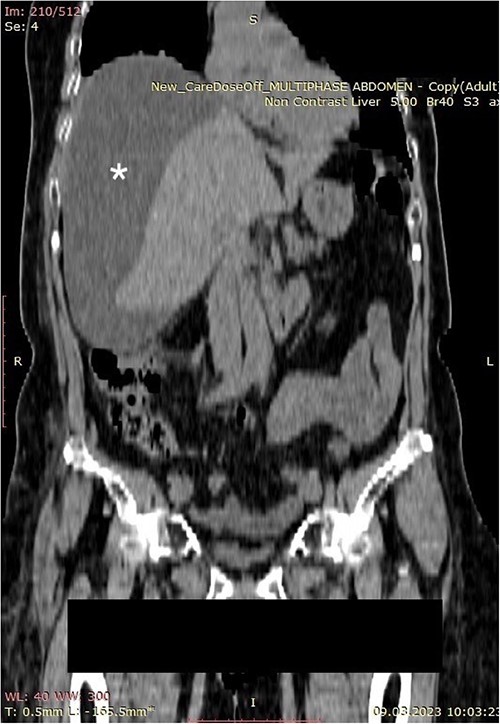

A 70-year-old female patient was transferred to our emergency department from another hospital with abdominal pain and vomiting in the past 2 weeks. The patient presented with clinical signs of acute abdomen. Physical examination showed diffuse abdominal tenderness. Abnormal laboratory findings comprehended Leucocyte count of 12.01 (3.5–10.0 × 109 g/L), Thrombocyte count of 456 (150.0–300.0 × 109 g/L), Neutrophil count of 9.7 (1.2–8.0 × 109 g/L), serum direct bilirubin value of 11.10 (0.0–8.6 mmol/L), and C-reactive protein value of 258 (0.0–5.0 mg/L). An abdominal computerized tomography (CT) scan revealed a large collection of fluid in the right hemiabdomen (Figs 1 and 2) and free gallstones in the abdominal cavity (Fig. 3).

Computerized abdominal tomography (axial scan) showing a large biloma in the right subphrenic region (asterisk).